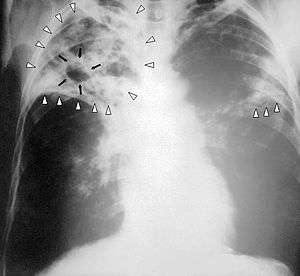

- Chest X-Ray - pericardial calcification (common but not specific), pleural effusions are common findings.[9]